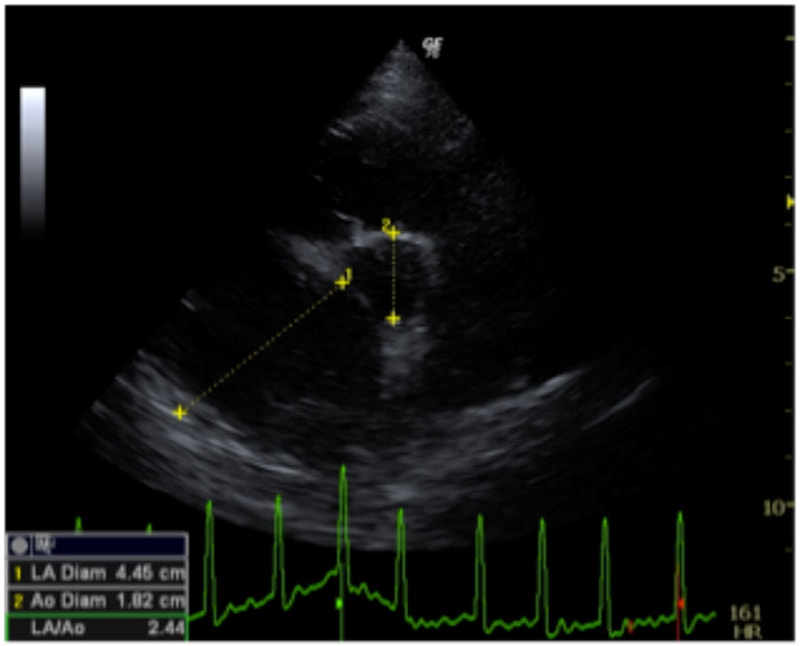

D:La/Ao比の重度拡大あり

左側胸壁心尖部領域を最強点とするLevine 5/6の収縮期性心雑音が聴取された。安静時にも咳が認められる。胸部レントゲン検査において重度の心拡大が及び肺水腫が認められた。超音波検査では、重度の僧帽弁閉鎖不全、三尖弁閉鎖不全が認められた。三尖弁逆流速度から肺高血圧症が示唆された。ACE阻害薬、ピモベンダン、硝酸イソソルビド徐放剤、ベラプロストナトリウム、利尿剤としてフロセミド及びスピロノラクトンを用いて治療を行っている。